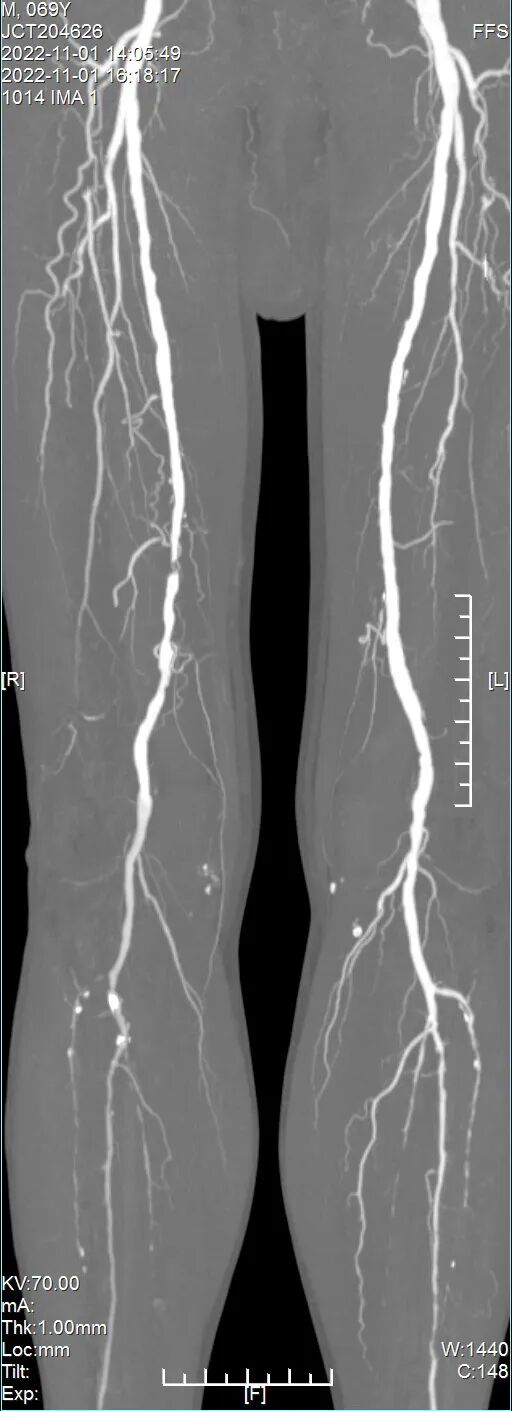

CTA:腹主动脉及双下肢动脉动脉粥样硬化改变,右股动脉中下段、胫后动脉起始段局部管腔重度狭窄。余管腔多发轻-中度狭窄(图1)。

(图1)